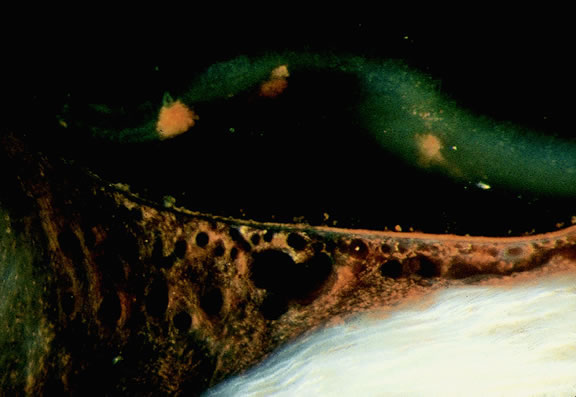

Many choroidal melanomas have a characteristic mushroom or collar button configuration that results when the tumor breaks through Bruch's membrane (Figs. 19, 20, 21, and 22). In such cases there is often secondary choroidal, subretinal, or vitreous hemorrhage. Dilated, intrinsic vessels often are evident in the mushrooming dome of nonpigmented melanomas. The vessels are obscured in more pigmented tumors.48

Fig. 22. Mushrooming head of choroidal melanoma contains dilated vessels which are located anterior to constricting gap in Bruch's membrane. (Hematoxylin-eosin, × 10.)

Choroidal melanomas initially arise in the stroma of the choroid. In early cases, the profile of the sectioned tumor is oval or almond-shaped, and its tissue usually appears relatively cohesive after fixation (Fig. 24). Although some tumors diffusely infiltrate the uvea, most uveal melanomas are relatively well-circumscribed tumors with distinct margins. In many cases the growing melanoma perforates Bruch's membrane and enters the subretinal space where its apex typically assumes a spherical shape that often is likened to a mushroom or collar button (see Figs. 19 to 22.). Dilated vessels often are found in the mushrooming head of the tumor because the ends of Bruch's membrane exert a compressive cinch-like effect on the waist of the tumor (see Fig. 22). Rupture of Bruch's membrane was present in 87.7% of 1527 large- or medium-sized melanomas examined in the COMS.84 Retinal invasion was present in nearly half (49.1%), and tumor cells were found in the vitreous body in one fourth.

Choroidal melanomas produce abnormalities in the overlying retinal pigment epithelium including atrophy, hyperplasia, and the formation of drusen and drusenoid material.92 The overlying retina often shows photoreceptor loss and may develop cystoid edema. The latter tends to be more common in slower growing lesions, especially choroidal hemangiomas. After Bruch's membrane has ruptured, the vessels located in the mushrooming head of the tumor are often quite prominent, reflecting vascular stagnation caused by the compression at the waist of the tumor (see Fig. 22). Aggregates of macrophages that have ingested periodic acid-Schiff (PAS)-positive lipofuscin pigment and melanin from the damaged retinal pigment epithelium can be found in the subretinal fluid (Figs. 39 to 41). These are evident ophthalmoscopically as clumps of orange pigment that serve as a clinical marker for an actively growing neoplasm.80,81